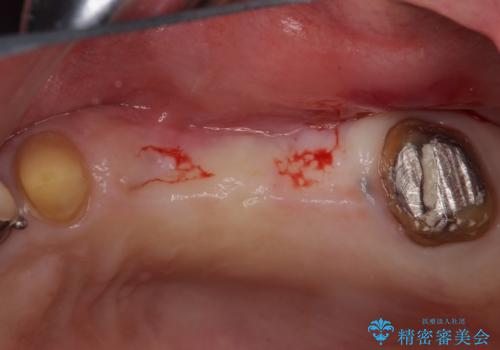

- 上の奥歯に装着されているブリッジが痛むとのことで来院された患者様です。

診察した結果、ブリッジの土台となっている歯が割れていたため、抜歯が必要となりました。

欠損している歯数が多いため、ブリッジによる補綴治療は困難と判断し、インプラントによる補綴治療を行うこととしました。

インプラントを埋入するために必要な骨の高さがなかったため、上顎洞底の粘膜を挙上しました。

手術後は処置部に痣や腫脹が出現したり、痛みが出たりしましたが、補綴治療後は咬み合わせが安定し、大変満足していただきました。